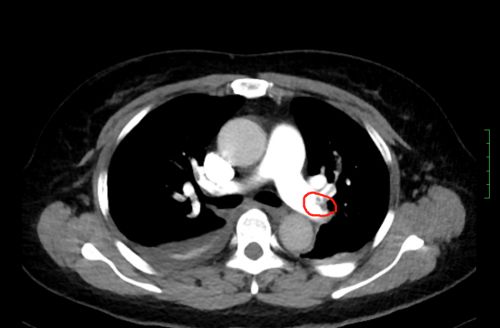

ct上可以看到,患者双侧肺动脉均有血栓形成。

情况十万火急,尹新民主任边现场组织抢救,边将情况汇报给向华副院长,向华副院长立即调度全院各相关科室予以协助。一场与生命的赛跑由此拉开!超声科紧急为患者进行床旁彩超,找到肺动脉栓塞的“罪魁祸首”为左下肢静脉血栓。在呼吸治疗组的协助下,医护人员携带转运呼吸机快速运送方女士至介入手术室。介入血管外科紧急安排了手术医生和手术间,由张永琎副主任医师等为患者施行“肺部血管造影”,明确诊断为双肺动脉急性栓塞,随即为其实施“双肺动脉尿激酶冲击溶栓、下腔静脉滤器植入术”。术后,患者肺动脉供血明显改善,血氧饱和度立即回升,被送往重症医学一科继续治疗。